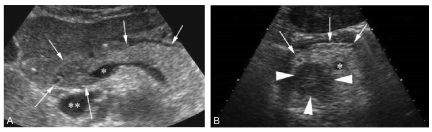

La visualisation directe de la tumeur est difficile en échographie abdominale transpariétale du fait de fréquentes interpositions digestives (figure 18.1). En revanche, l’écho-endoscopie, qui nécessite une anesthésie, visualise facilement la lésion, très hypoéchogène. Mais, peu disponible et invasive, elle n’est jamais réalisée en première intention.

Fig. 18.1. Échographie d’un pancréas normal et d’un pancréas tumoral. Exemple de pancréas normal en échographie (flèches) (A) : la glande est plutôt hyperéchogène. Elle est située au contact de la naissance de la veine porte (∗) ; la tête du pancréas est située en avant de la veine cave inférieure (∗∗). Tête du pancréas (B, flèches) avec présence d’une lésion d’adénocarcinome ronde et très hypoéchogène (têtes de flèches).

Source : CERF, CNEBMN, 2022.